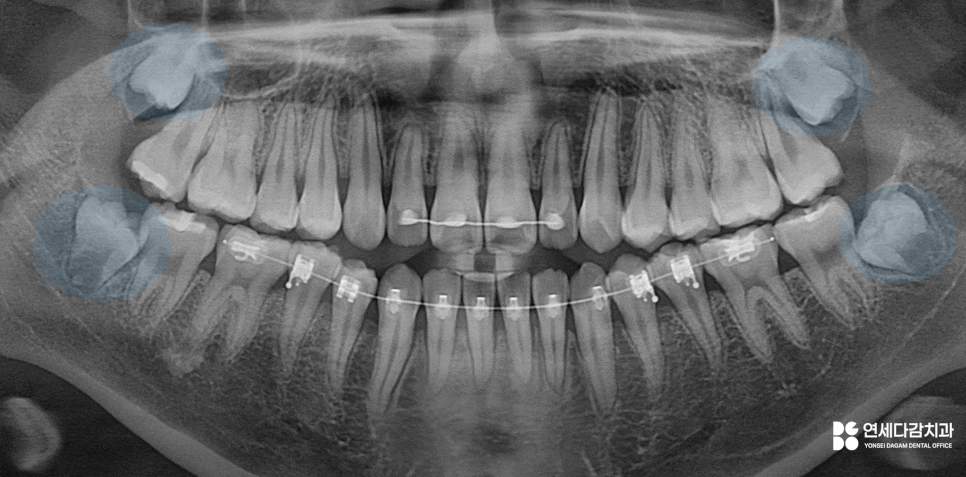

가락동 치과 에서 설명하는 케이스는

교합면이 혀쪽으로 향해 있으며,

진료 접근을 위해서는 잇몸 절개 후

골 삭제가 필요할 것으로 판단됩니다.

2026.01.06

더불어, 아래쪽 매복 어금니 같은 경우

치근단 하방 하치조신경관과 근접할 때가 많아

사전에 정확한 거리 관계를 파악합니다.

자칫해서 진료 도중 자극을 줄 수 있으며

일시적으로 감각 마비 같은 후유증이 남을 수 있고

드물게는 영구적으로 남는 사례도 있습니다.